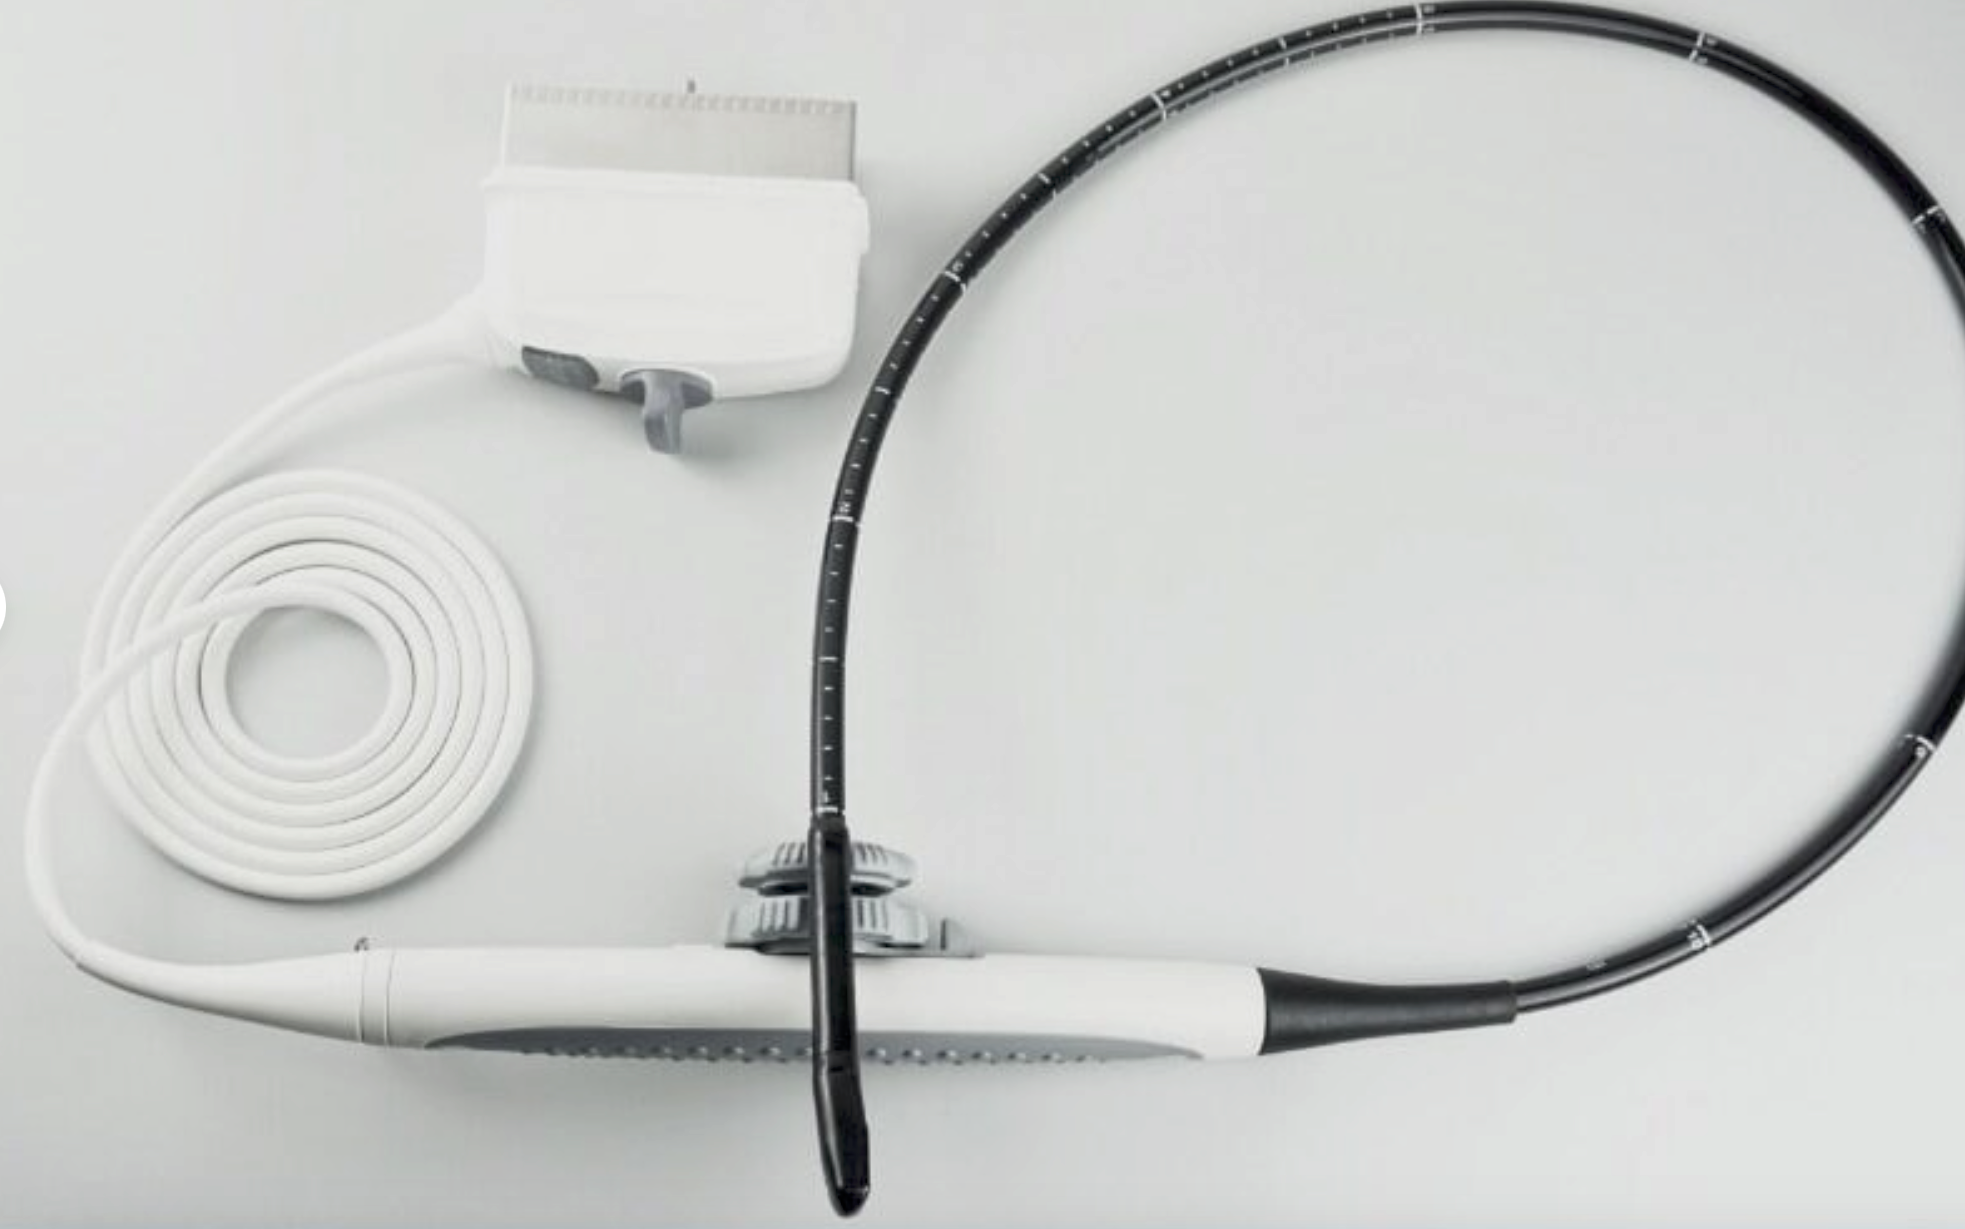

Optional: Convex probe 3.5MHz: Linear probe 7.5MHz/Transvaginal probe 6.5MHz